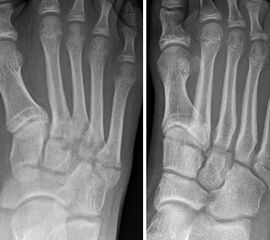

Sir Robert Jones erlitt beim Tanzen eine Fraktur seines 5. Mittelfußknochens, „three-fourths of an inch [1.9 cm] from its base“. 1902 publiziert er eine erste Fallserie mit seinem Fall und fünf weitere Patienten mit einer MT V Basisfraktur. Seitdem wurden verschiedene Frakturlokalisation im Bereich der MT V Basis als Jones Frakturen bezeichnet, was den Begriff sehr unscharf gemacht hat. Insgesamt sind in der Literatur mehr als 20 verschiedene Klassifikationen der MT V Basisfraktur beschrieben. Im Folgenden sollen die beiden am häufigst angewandten vorgestellt werden. Die Frakturklassifikation erfolgt anhand der schrägen Röntgenaufnahme.

Illustration der Lawrence und Botte Klassifikation:<br>

Zone I: Avulsionsfraktur der Tuberositas <br>

Zone II: Jones’ Fraktur <br>

Zone III: Diaphysäre Stressfraktur<br>

Abbildung 1

Die in der Literatur am häufigsten verwendete Klassifikation ist die 1993 publizierte, anatomische Klassifikation von Lawrence und Botte 6. Diese basiert auf einer retrospektiven Fallserie und unterscheidet drei Frakturzonen (Abb. 1).

Zone II befindet sich auf Höhe der Articulatio zwischen MT IV und V. Die Zone I liegt proximal, die Zone III distal davon. Interessanterweise vermischen Lawrence und Botte Unfallmechanismen (Avulsionsfraktur/Stressfraktur) und deskriptive Terminologie (Jones’ Fraktur) in ihrer Klassifikation. Eine Vereinfachung dieser Klassifikation publizierten Polzer et al. 2012 7. Basierend auf den Ergebnissen von sechs prospektiven Behandlungsstudien (systematische Literaturrecherche), schlussfolgerten die Autoren, dass Lawrence und Botte Zone I und II Frakturen zusammengefasst werden könnten (Metaphysäre Frakturen). Zone III Frakturen werden als Meta-Diaphysär beschrieben.